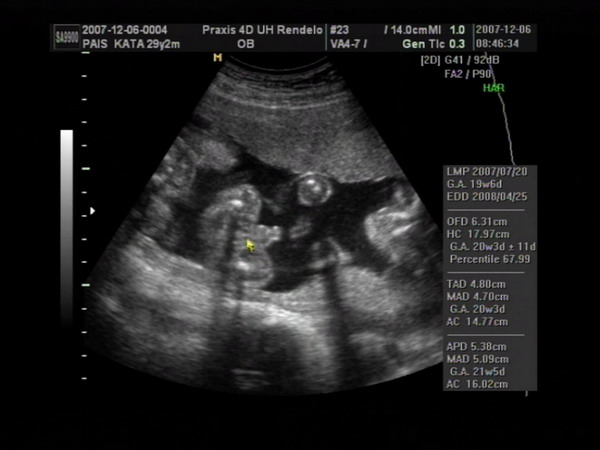

Végre sikerült olyan formátumot csinálni a 4D-s képeinkből, amit ide is fel tudok tenni, úgyhogy büszkén fel is teszem a fotókat :).

Csenge nagyon fotogén volt:

Kép

Marci megpróbált elbújni a medencecsontom mögé, mert a tesója állandóan az ő vállaira akarta feltenni a lábait - ráadásul a feje fölött volt vmi, ami árnyékot vetett a kobakjára:

Na és az egyértelmű bizonyíték arra, hogy Csenge kiscsaj:

Itt pedig a kis pöcsös látható:

Kata

Meli, elméletileg a kiscsaj van alul, és felette a kisfickó - de ez nem 100%, mert dec. 6-án voltunk 4D-n, és azóta lehet, hogy megfordultak. Tegnap voltam dokinál, ő viszont már azt mondta, hogy a végleges helyükön vannak a törpék, már nincsen helyük megfordulni (az viszont nem látszott tegnap, hogy melyik van alul-felül). Mikuláskor kb. 35 dkg-ok voltak, tegnap csak a fejüket mérte a doki bácsi. Minden rendben van velük, de harántfekvéses mindkettő :roll: